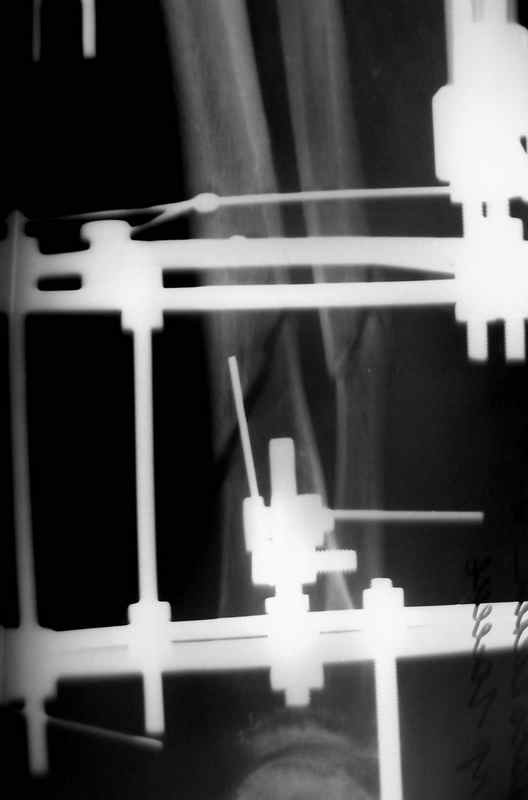

Больная 54 года, 5 м. назад открытый оскольчатый перелом 2-3 тип, Первично ЧКДО, открытое ведение раны, при этапных некрэктомия " ушел" осколок внутренней стенки б/бецовой кости, 7 сутки пластика м/тканями ,вторичные швы.

Контакт отломков только по спирали наружной стенки,заживление раны полное, на 3-4 месяце ЧКДО воздействие на регенерацию микродистрациями , 5 месяц снят аппарат по причине нестабильности и реакции м/тканей. В данный момент проблем с тканями нет, на Р-граммах псевдоартроз, клинически подвижность,больная ходит в ортезе с дозированной нагрузкой.Местно рубцовый процесс 3х5 в зоне перелома.

Будьте добры послать снимки до операции . а также после операции, на которых видна компановка аппарата Илизарова. Кстати на представвленных рентгенограммах в аппарате есть спица с напайкой, проведённая проксимально перелома через обе кости... Если можно, объясните необходимость такого проведения.

Там две спицы с напайкой дистально и проксимально и обе только через 1 кость

Встречно-боковая компрессия по классике, удержать отломки от смещения по ширине